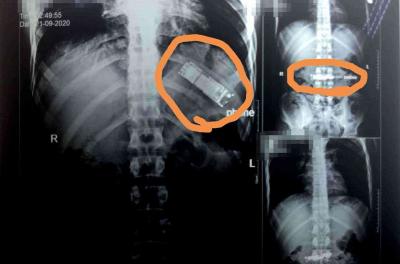

كشفت أشعة تلفزيونية تم إجراؤها بمستشفيات بنها الجامعية في مصر عن وجود هاتف محمول في معدة شخص، مؤكدةً ابتلاعه للهاتف منذ 7 أشهر تقريباً.

وقال استشاري أورام الصدر وأستاذ جراحة القلب والصدر والمناظير بكلية الطب للجامعة، حسبما نشر موقع "اليوم السابع"، اليوم، إنه خلال إجراء أشعة تليفزيونية على صدر وبطن المريض البالغ من العمر 28 عاماً، تم اكتشاف وجود هاتف محمول في معدته، موضحاً أن المريض أكد ابتلاعه للهاتف منذ 7 أشهر على سبيل المداعبة مع أصدقائه دون أن يعلم أي فرد من أبناء أسرته، وأنه كان يظن أن الهاتف سيخرج بمجرد حدوث استرجاع بالمعدة مرة أخرى.

وأضاف الاستشاري أنه تم تحويل المريض إلى قسم الجراحة العامة بالمستشفى، لافتاً إلى إعداده حالياً ووضعه بقائمة الجراحات تمهيداً لإجراء الجراحة سريعاً والتعرف إلى نوع الهاتف وكيفية بلعه. |